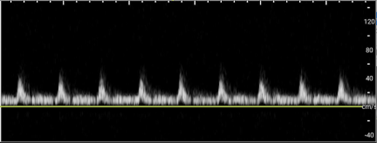

• A healthy testicle should appear oval-shaped and roughly 3–5 cm in length, by 2–3 cm in width depending on the age. Testicles have a homogeneous appearance with a medium-level echogenicity (like other solid organs). They are smooth and uniform throughout when healthy. Start by fanning through the testicle in transverse and longitudinal orientations to get a general assessment. When applying color Doppler to a well perfused testicle, there should be uniform, low velocity arterial and venous blood flow throughout the parenchyma. Vessels may appear pinpoint, linear or branching. Using spectral Doppler, the velocity of specific vessels can be measured. Arterial flow will appear as a brisk upstroke and sharp downstroke reflecting the cardiac cycle. Venous flow has a continuous velocity with less variation, often described as a “venous hum” (Images 6 and 7).7

Torsion - image 7.pngImage 7. Venous flow on Spectral Doppler.